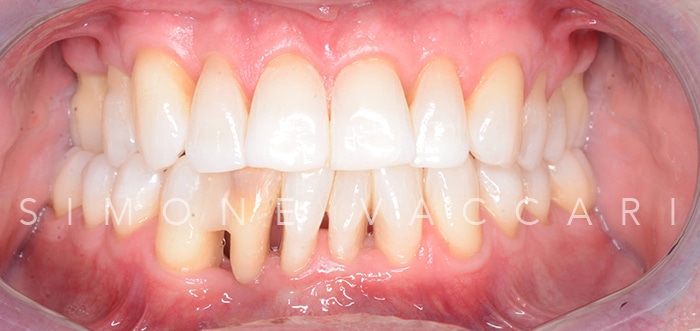

Michele bocca dopo la cura della parodontite Dopo

Michele dopo la cura della parodontite Dopo